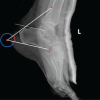

Case illustration 1: Depicted Fig. 2 shows the X-ray image of a patient who presented as type A of AO closed distal tibial fracture and comminuted distal fibula fracture with a tense swelling over ankle. He was managed primarily with open reduction and internal fixation with a plate for the fibula to maintain the length and proceeded with a hybrid external fixator for tibia. He was followed up for fracture union, and the hybrid external fixator was removed at 14-week postoperative period after complete union and ankle mobilization exercise were given. After an intensive physiotherapy session for ankle stiffness, the patient had achieved complete range of movements (Fig. 2). Case illustration 2: Patient presented with open fracture Gustilo Anderson type 3A, AO type C3 proximal tibial fracture with diabetes mellitus. He was operated with wound debridement and hybrid external fixator construct and followed up with serial X-rays, in which union occurred at 16-week postoperative period without any complications (Fig. 3). Case illustration 3: Patient presented with open Gustilo Anderson type 1, type A of AO classification of distal tibial fracture and displaced fibula fracture. He was operated with open reduction and internal fixation with plates for fibula fracture to maintain the leg length then a hybrid external fixator for the distal tibia. Union was achieved at 14-week postoperative period (Fig. 4).